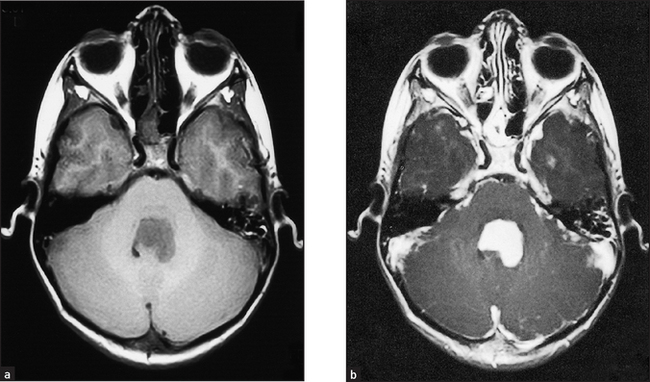

Some common examples of important diagnostic scans are shown in Figures 36.2–36.8 and 36.10.

Figure 36.5 Cerebellar tumour This is the typical appearance of a brain tumour on MRI, in this case a cerebellar medulloblastoma. (a) The tumour has a low signal on spin-echo T1-weighted images. (b) After injection of gadolinium (a contrast agent) the tumour enhances avidly, indicating a breakdown of the blood–brain barrier. (Adam A. Grainger & Allison’s diagnostic radiology, 5th edn. Churchill Livingstone, 2008.) Churchill Livingstone